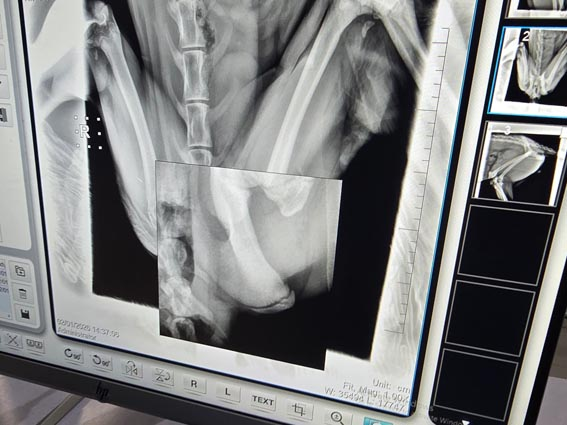

CCF France fait un don de 3’500 euros au CCF Somaliland pour l’achat d’un appareil de radiographie

Au CRCC (Cheetah Rescue and Conservation Centre – Centre de sauvetage et de protection des guépards) du Cheetah Conservation Fund, les soins vétérinaires ne sont pas occasionnels, ils sont quotidiens. Beaucoup des guépards que nous sauvons arrivent blessés, mal nourris et/ou souffrant de conditions causées par des conflits avec les humains, le trafic illégal ou un mauvais développement précoce.

Une machine à rayons X sur place permettra à notre équipe vétérinaire du Somaliland de :

- Diagnostiquer rapidement et avec précision les fractures, les blessures articulaires et les lésions squelettiques;

- Identifier les problèmes congénitaux ou développementaux chez les petits avant qu’ils ne s’aggravent;

- Surveiller la guérison et la récupération sans transports stressants répétés;

- Prendre des décisions éclairées concernant la gestion de la douleur, la chirurgie ou la rééducation;

- Agisser immédiatement en cas d’urgence, lorsque le temps et la gestion peuvent tout signifier

Sans cet équipement, chaque blessure suspectée devient un risque logistique avec de longs trajets, un stress supplémentaire pour des animaux déjà vulnérables, un traitement retardé et une clarté de diagnostic limitée.